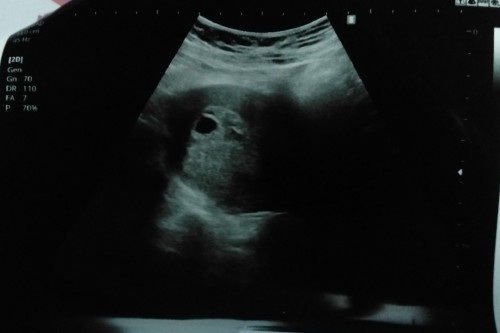

ไปเมื่อวานนี้ค่ะคุณหมอบอกเป็นท้องลม ไม่ฉีดยากันแท้งให้ปล่อยให้หลุดตามธรรมชาติค่ะ

รีบไปหาหมอนะคะ เสี่ยงแท้งคุกคามค่ะแม่